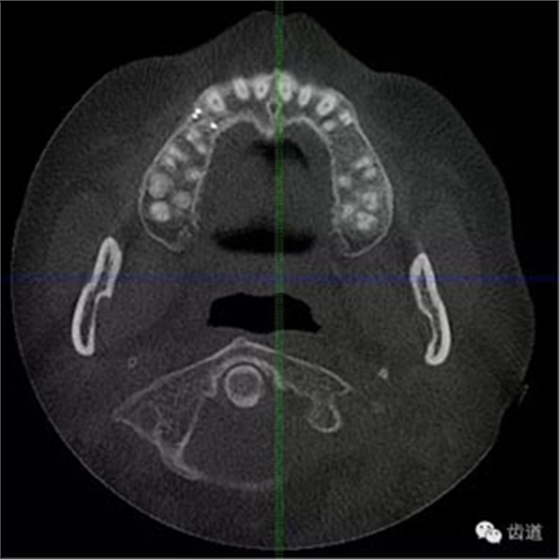

處理:1.建議CBCT檢查。

好的開(kāi)始就是成功的一半。通過(guò)CBCT了解根管的位置,形態(tài),方向。

檢查顯示:近頰及腭根充填恰填,遠(yuǎn)頰根管內(nèi)有少許充填物影像。根尖明顯低密度影像。